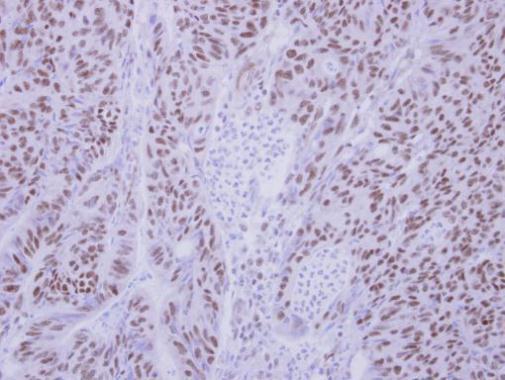

Immunohistochemical analysis of paraffin-embedded human colon carcinoma, using BS69 antibody(GTX103403) antibody at 1:250 dilution.

Antigen Retrieval: Trilogy™ (EDTA based, pH 8.0) buffer, 15min